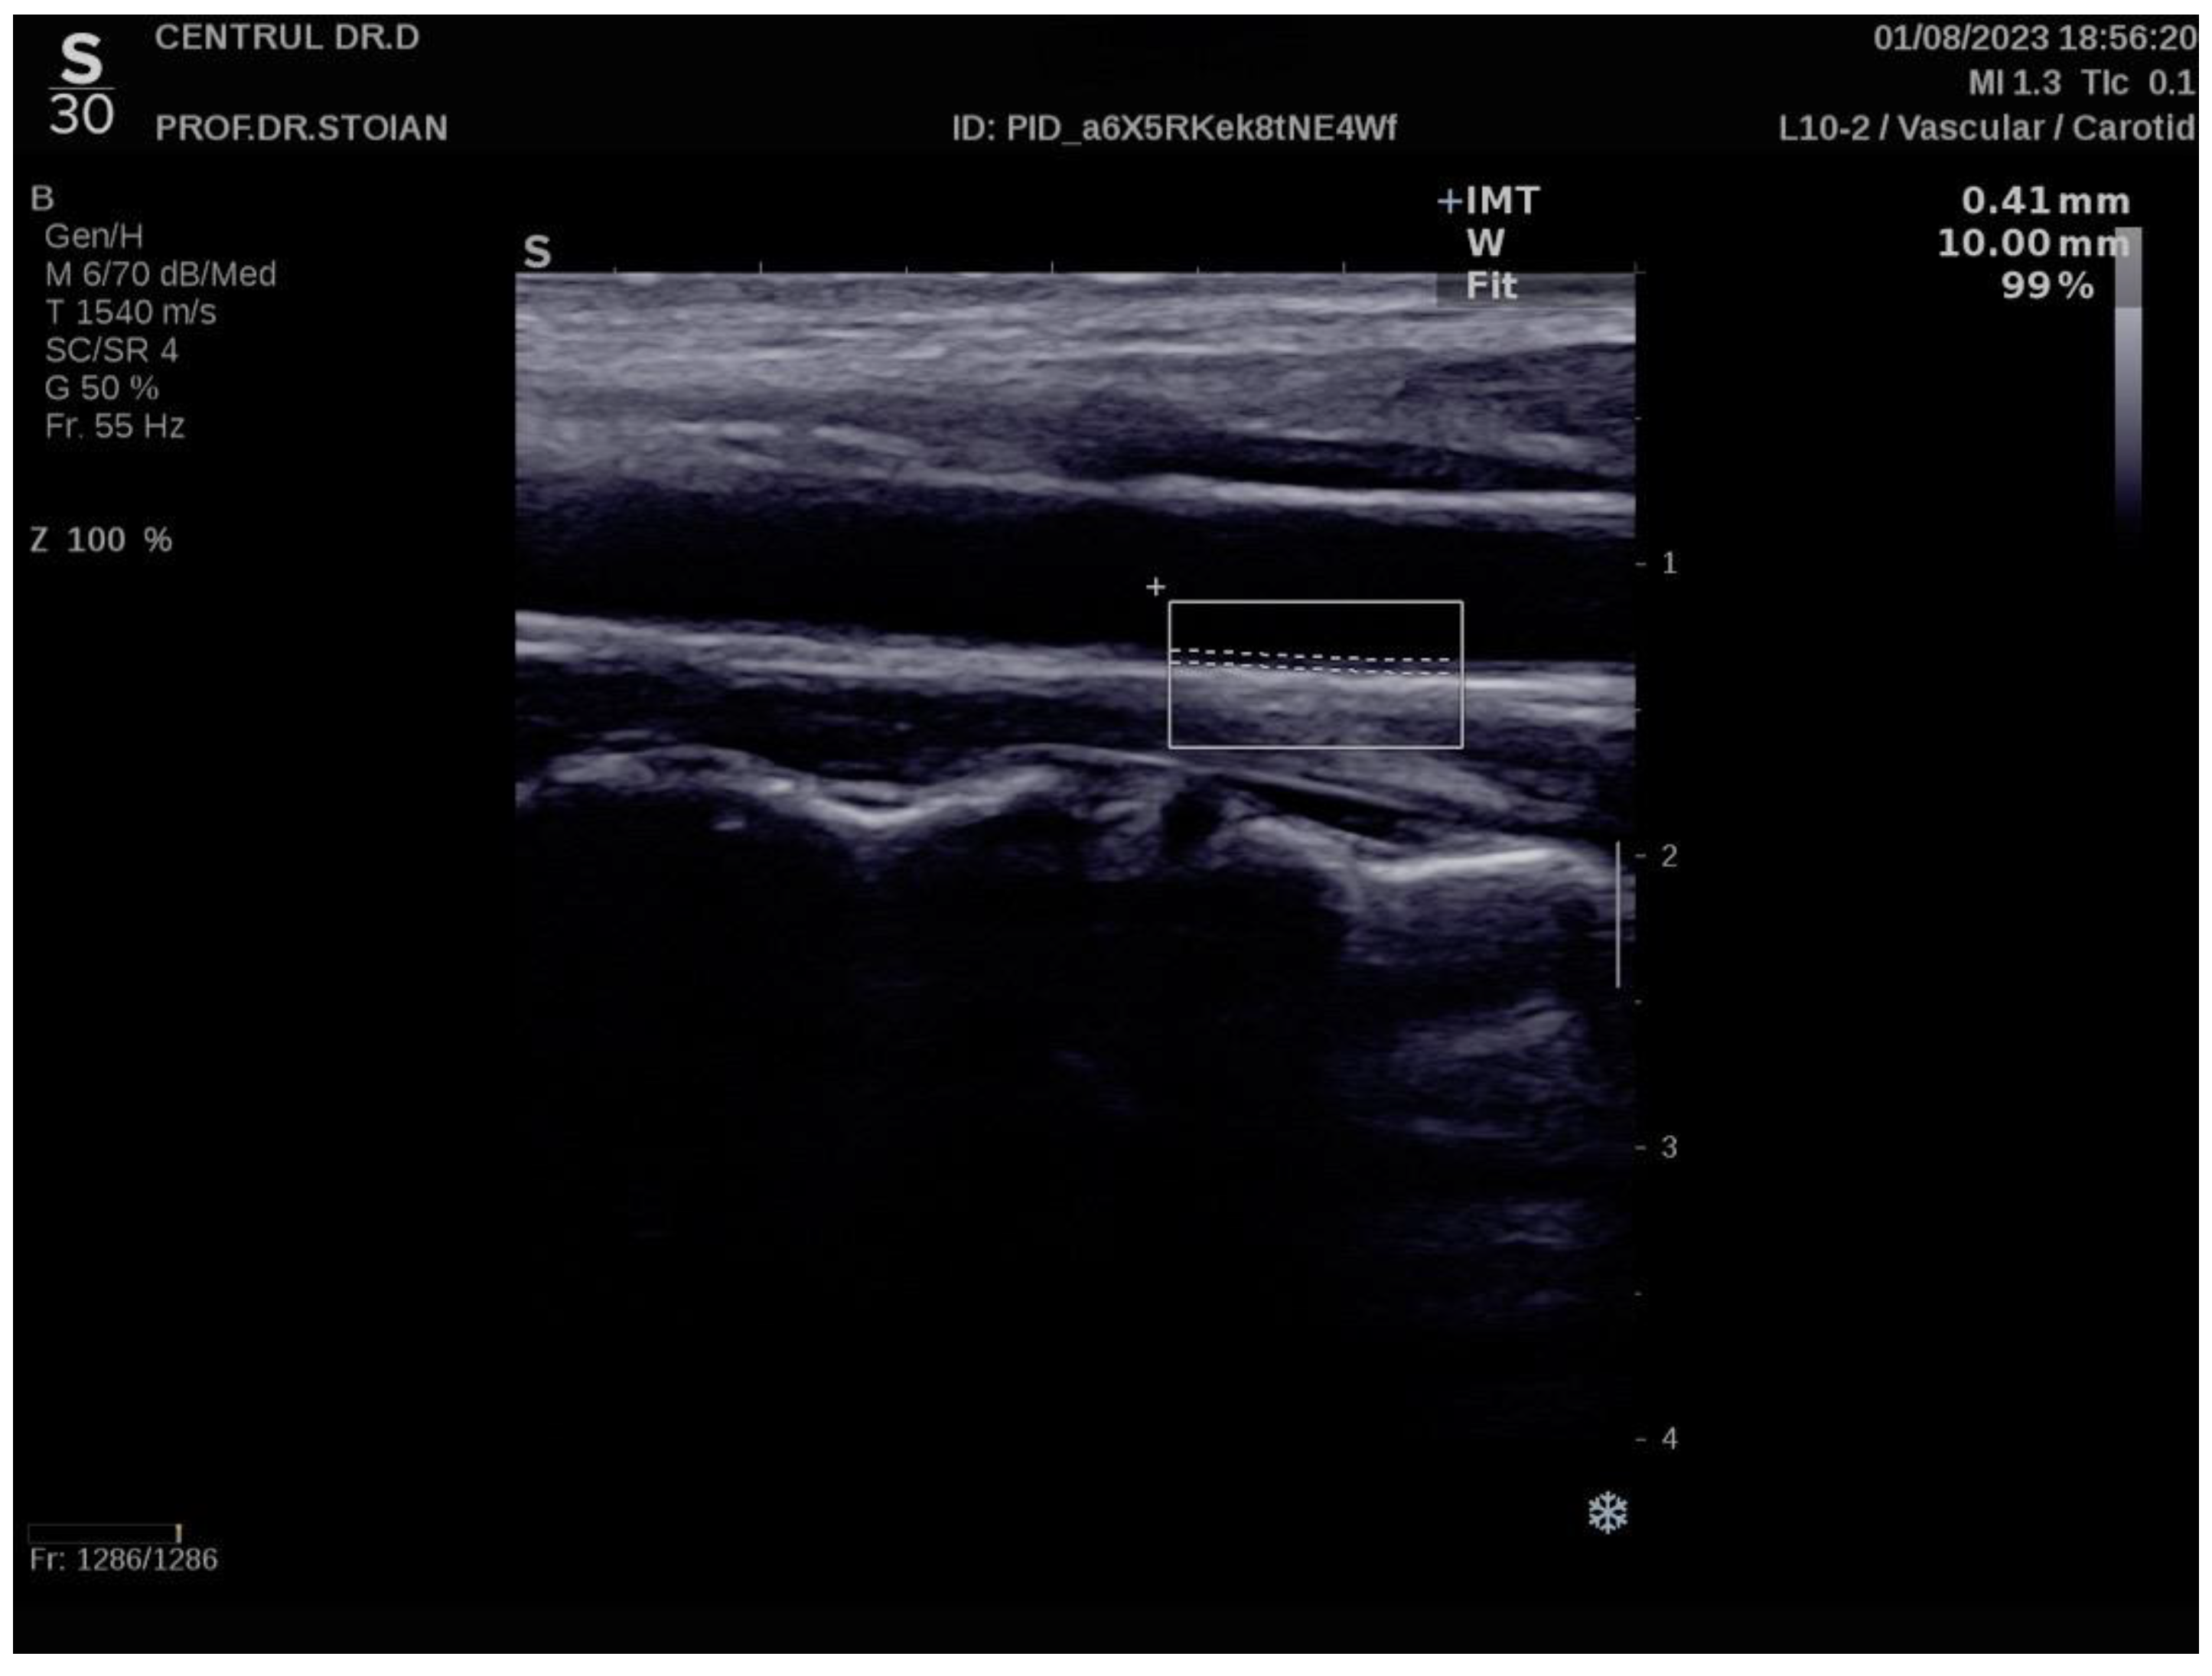

The Aixplorer MACH 30 ultrasound system (SuperSonic Imagine, Aix-en-Provence, France) was used to conduct an ultrasonographic assessment of carotid intima-media thickness. A certified and highly experienced sonographer conducted carotid ultrasonography on each participant included in the study. The procedure involved carefully positioning each subject to ensure optimal visualization of the carotid artery and applying a conductive gel to facilitate sound wave transmission. The sonographer then meticulously scanned the carotid arteries, using appropriate transducer settings based on individual anatomical characteristics, such as neck structure and adipose tissue distribution: SL 18-5 (5-18 MHz) or SL 10-2 (2-10 MHz). The CIMT values were automatically computed by the advanced software embedded within the ultrasound system (SuperSonic Imagine, Aix-en-Provence, France). This software analyzes the ultrasound images in real-time, providing precise measurements of the intima-media thickness without requiring manual calculation, ensuring both accuracy and efficiency in the evaluation process. The ultrasound images were captured during the end-diastolic phase, identified by the occurrence of the R wave on the electrocardiogram, ensuring consistency in arterial relaxation and minimizing variability in measurements [73]. For each participant, six separate CIMT measurements were taken, with three measurements performed on both the left and right carotid arteries. The measurements were carefully averaged to produce a mean CIMT value, which was subsequently used for analysis in the study. This approach helped to enhance the precision and reliability of the data by accounting for natural variations in arterial thickness across different locations and ensuring that the final CIMT value represented an accurate reflection of each patient's vascular status. To obtain optimal visualization of the right and left common carotid arteries, the subject is positioned in a supine position and instructed to extend their neck backward as far as comfortably possible, enhancing exposure of the cervical region. Additionally, the examiner carefully chooses the most suitable ultrasound transducer, ensuring the correct frequency range is used to maximize image clarity and resolution for accurate assessment of the CIMT. The scanning procedure begins with a transverse approach, starting at the clavicle and moving upward along the neck to identify the carotid bulb and the bifurcation of the common carotid artery into the internal and external carotid arteries. Once the carotid bulb is located, the examiner transitions to longitudinal scanning, allowing for a detailed assessment of the arterial walls and more precise measurement of the CIMT along the length of the artery. This systematic approach ensures thorough visualization of both the structure and flow characteristics within the carotid arteries. In this section, the carotid bulb is visualized on the left side of the ultrasound screen. Measurements are taken from the posterior wall of the carotid artery, specifically 1 to 2 cm distal to the carotid bulb. This location is chosen to avoid the geometrical irregularities of the bulb itself and to obtain accurate and consistent CIMT values from a more uniform segment of the arterial wall [74,75]. At end-diastole, the image is frozen, and the software automatically measures the CIMT in the examiner's selected region of interest, ensuring consistency and precision [76,77].

Figure 6 illustrates an example of CIMT evaluation for the left carotid artery obtained using this method in a normoweight subject, whose CIMT value falls within optimal limits. In contrast, Figure 7 depicts an elevated also left CIMT value of 1 mm, observed in a patient with grade II obesity. It is important to note that personal data of the evaluated subjects are not displayed to ensure confidentiality.

Figure. Example of a normal left CIMT measurement in a normoweight patient using the Aixplorer MACH 30 ultrasound system.

Preprints 147944 g001